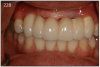

An implant most closely replicates the feel of a natural tooth. Once it is osseointegrated, many patients cannot differentiate an implant from a natural tooth. Furthermore, dental implants do not decay or need a root canal. Even though the cost is slightly more than a bridge, it is a great investment for the future, as implants usually last longer than a bridge. A 10-year report on posterior single implants shows a success rate of 97%.29 Once an implant is placed, an integration/healing time of approximately 4 months is necessary before final crown is placed. A temporary crown can be placed the same day the implant is placed. (Figures 11A-E)

The implant prosthesis delivery appointment is similar to that of a crown and bridge. (Figure 22B) If the prosthesis is screw retained, then no cement is necessary and an occlusal filling material, such as composite, is necessary. After bite check, the patient is taught how to maintain the restoration. (Figure 22C)

Figure 22B – Metal-free fixed partial denture cemented on abutments

Figure 22B

Figure 22C – Final smile line

Figure 22C